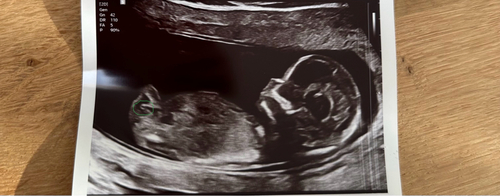

Vandaag de 13 weken echo gehad met 13+1 wat denken jullie

🩷